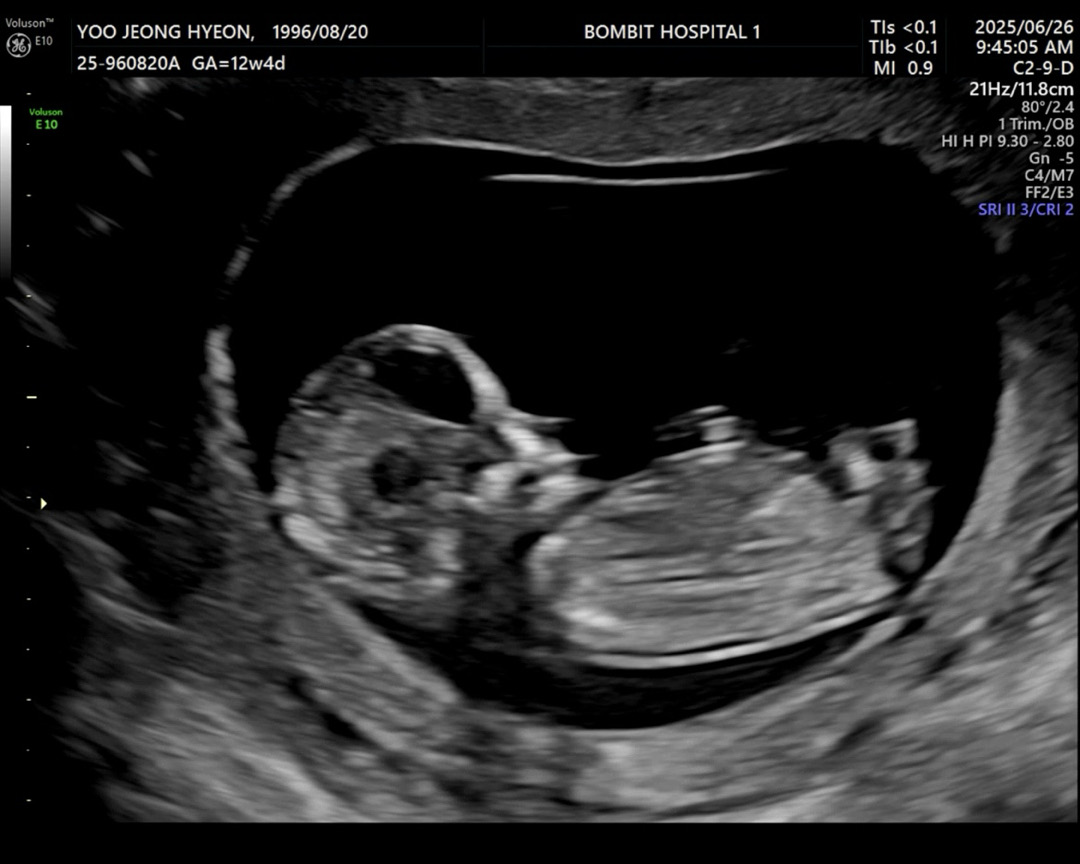

각도법 고수님들 한번만 봐주세요🙇🏻♀️

아기가 너무 움직여서 캡쳐가 제대로 안 따졌네요,,ㅋㅋㅋㅋㅋ ㅠㅠ 뭐가 성기 돌기인 지 모르겠어서,, 각도법 한 번만 봐주세요 고수님들🥹